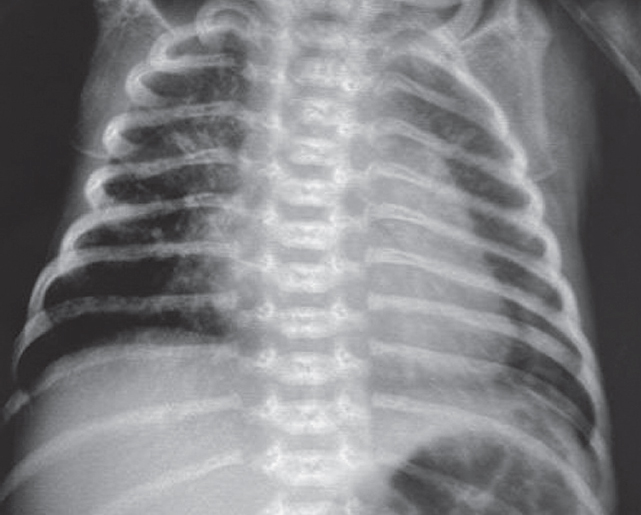

На этом фоне отмечается выраженный положительный эффект в виде увеличения SpO2 с 7–23 до 90 %, на контрольной рентгенограмме сразу после введения порактанта альфа (рис. 3) отмечается незначительное улучшение пневматизации левого легкого, сохраняется свободный воздух в правой плевральной полости.

Рис. 3. Рентгенограмма органов грудной клетки новорожденного после монобронхиального введения сурфактанта

Fig. 3. Chest X-ray of newborn after monobronchial surfactant administration

На контрольной рентгенограмме через 6 ч после манипуляции сохраняются признаки правостороннего пневмоторакса, отмечается неравномерное восстановление воздушности левого легкого. Снизить параметры ВЧО ИВЛ не представлялось возможным. В последующем отмечено прогрессирование явлений дыхательной недостаточности с десатурацией (SpO2 46 %), по анализу газового состава венозной крови отмечается выраженная венозная гипоксемия (рО2 13 мм рт. ст.), гиперлактатемия (6,7 ммоль/л). Сохраняется выраженная артериальная гипотензия, в связи с чем скорость введения адреналина увеличена до 0,2 мкг/(кг · мин), на этом фоне достигнута стабилизация.

В левый главный бронх повторно введен порактант-альфа. После выполнения манипуляции отмечается клинико-рентгенологическое улучшение (рис. 4) — увеличение SpO2 до 90 %, положительная динамика газового состава крови.

Рис. 4. Рентгенограмма органов грудной клетки новорожденного после повторного монобронхиального введения сурфактанта

Fig. 4. Chest X-ray of newborn after repeated monobronchial administration of surfactant